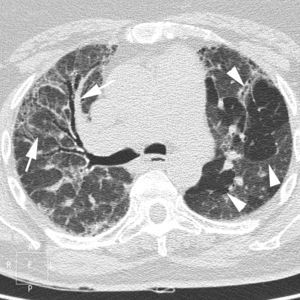

En la TCAR, la fase aguda de la AAE se caracteriza por la presencia de un patrón pulmonar difuso en «vidrio deslustrado», un patrón nodulillar o un patrón mixto, asociado muchas veces a áreas parcheadas de atrapamiento aéreo. En las fases crónicas, la presencia de un patrón reticular con desestructuración y retracción de los ejes broncovasculares refleja la presencia de fibrosis. Es frecuente el hallazgo asociado de áreas focales de atrapamiento aéreo (fig. 12)51.

Imagen TCAR centrada en lóbulos superiores en un paciente con alveolitis alérgica extrínseca en fase crónica, que destaca la presencia de opacidades reticulares, bronquiectasias de tracción y «vidrio deslustrado» (flechas), asociado a áreas focales de atrapamiento aéreo en lóbulo superior izquierdo (cabezas de flecha).